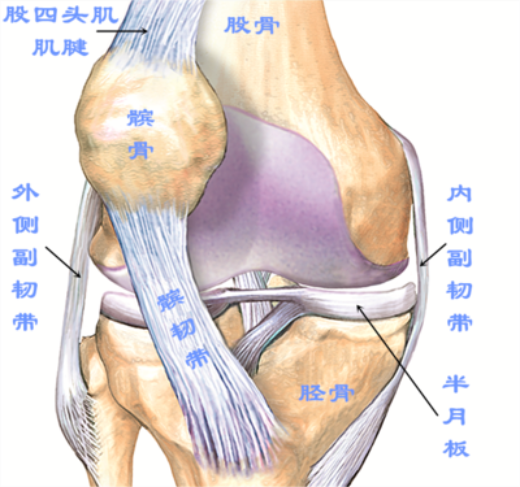

半月板损伤

半月板损伤是引起病理性弹响最常见的一种原因声音清脆,发生频率高,常伴有关节交锁(卡住、疼痛),这常是运动不慎扭伤所致。较轻的半月板损伤并无痛感,走路甚至慢跑都不受影响,易被忽视,但长期不治疗容易造成关节软骨损伤,最终可能导致骨性关节炎,甚至要进行膝关节置换。

交叉韧带损伤

前后交叉韧带损伤的患者,尤其是前交叉韧带损伤的患者,如果有比较明显的撕裂或断裂,应尽早进行关节镜手术治疗。如果一味拖延,可能会导致交叉韧带的残端绞锁卡顿于髁间窝,会出现弹响。

骨性关节炎

骨性关节炎通常是由于关节软骨或半月板病变,使髌股关节和胫股关节软骨磨损,导致关节之间摩擦增大,活动膝关节的时候就会发生响声,声音低钝,频繁发生,并多伴有局部肿痛。若出现以上情况应积极治疗,并配合膝关节功能训练,可以很好地改善症状。如果不加以重视,迁延日久导致软骨磨损严重,疼痛症状明显,则需要进行关节置换手术。

除此之外髂胫束综合征、髌股关节综合征、滑膜皱襞综合征、滑膜软骨瘤病、半月板钙化、先天性膝关节脱位、股二头肌腱滑脱等均可引起膝关节出现弹响。